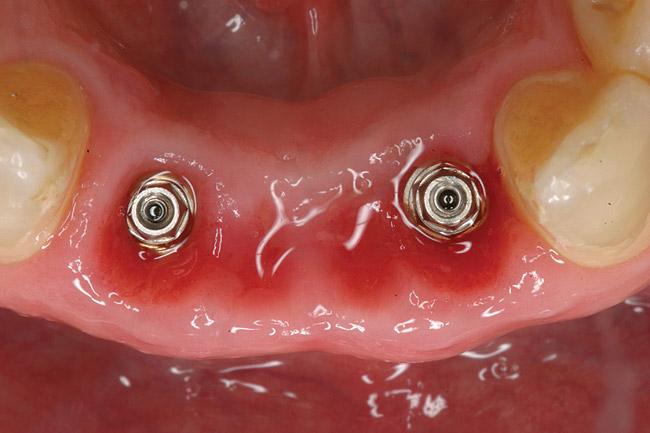

Figure 5  Tapered implants with conical transgingival abutments and temporary cylinders in place.

Figure 5

Figure 9  Stage 1 surgery.

Figure 9